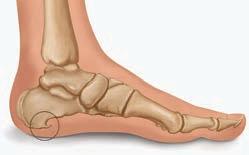

МОЖЕТ ЛИ БОЛЕТЬ КОЛЕНО

ИЗ-ЗА ПЛОСКОСТОПИЯ? ЧТО В ЭТОМ СЛУЧАЕ ДЕЛАТЬ?

Плоскостопие – одна из наиболее известных патологий стопы. При этой болезни происходит снижение высоты сводов – естественных изгибов подошвы. Уменьшение сводов ведет к снижению амортизации и перегрузке всех суставов. Плоскостопие может врожденным и приобретенным, поперечным, продольным или комбинированным.

вместной работой при ходьбе. При этом закономерными являются два механизма влияния стопы на коленный сустав: • При «заваливании» или пронации стопы (что и характерно для плоскостопия) происходит вращение голени внутрь. При этом больше нагружаются наружные отделы коленного сустава.

• Супинация стопы (нагрузка больше на наружную сторону) вызывает вращение голени кнаружи. Большую нагрузку испытывает внутренняя часть сустава.

В медицине есть закономерность: сначала болит не причина проблемы, а страдающие от нее отделы. Поэтому сама плоская стопа часто совершенно безболезненна. Боли, связанные с этой проблемой, обычно проявляются в коленях, тазу, пояснице и шее. Лишь на последних стадиях плоскостопия неприятные ощущения доминируют именно в проекции суставов стопы.

КАК СВЯЗАНЫ КОЛЕНО И СТОПА?

Коленный сустав – ближайший к стопе

Помимо прямого влияния на положение голени и колена, от состояния стопы зависит и безопасность коленного хряща. Своды стопы – аналог рессор автомобиля, их основная задача –гасить

ударные нагрузки до влияния на вышележащие отделы. Утрата амортизации стопы приводит к перегрузке и травме хряща, что в конце концов вызывает артроз и хроническую боль в колене.

Наиболее эффективно улучшают амортизацию стоп и защищают колени ортопедические стельки. Выступы супинаторов не только поддерживают правильную форму сводов, но и стимулируют мышцы-стабилизаторы. В зависимости от формы и материала стельки могут больше амортизировать, массировать, разгружать или стимулировать стопы.

• Ортопедические стельки для повседневной обуви. Оснащены каркасом, который стимулирует мышцы и корректирует своды.

• Спортивные модели. В таких изделиях акцент сделан на максимальную амортизацию. Они подходят для бега, игровых видов спорта, катания на лыжах и прочего.

• Стельки для обуви на высоком каблуке. Модельные стельки имеют уникальную форму для поддержки переднего отдела стопы.

• Индивидуальные ортопедические стельки. Именно в таких изделиях можно добавлять специальные элементы для изменения позиции колена, поворота стопы и голени.

Если боль присутствует долго, разбираться нужно и с самим коленом. Хорошо справляются с болью эластичные бандажи с силиконовыми вставками. Они мягко поддерживают и массируют сустав, улучшают кровоток и комфортно стимулируют стабилизирующие мышцы. p